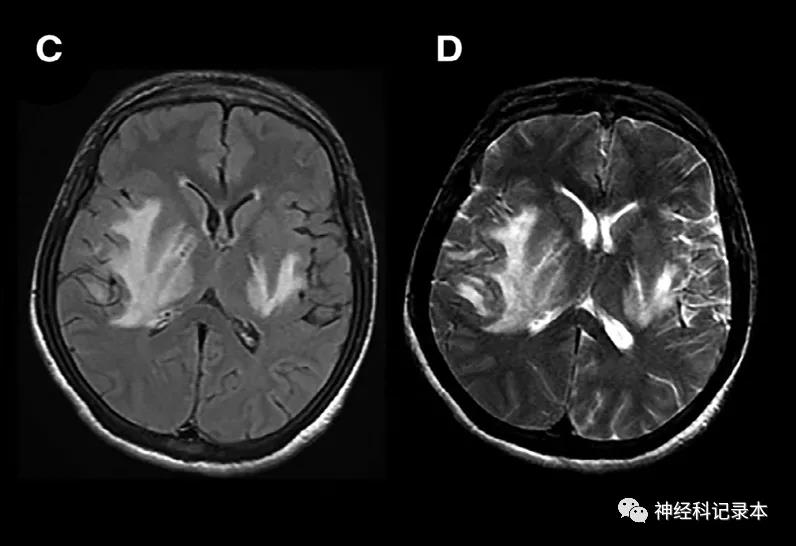

豆状核叉征是一种罕见的MR征,累及内囊后肢、外囊,并向后延伸,外观形似西餐时使用的叉子。

影像表现为豆状核在T2WI、FLAIR上基本对侧的异常高信号(T1WI上呈低信号),CT表现为豆状核低密度。